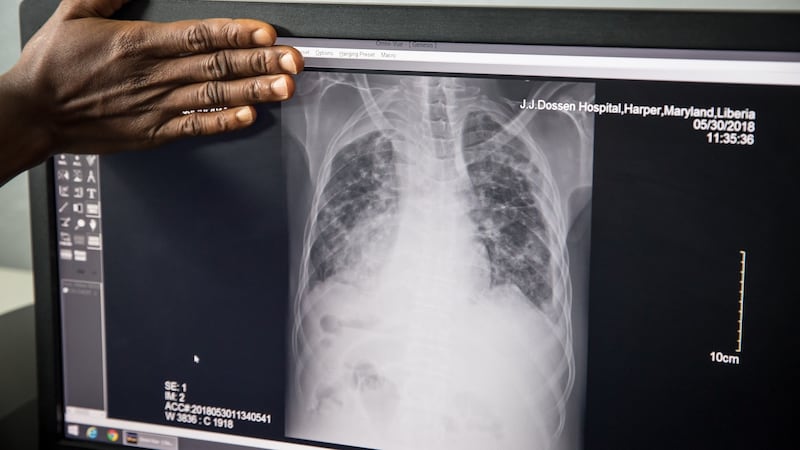

Augustine (26) has multi-drug-resistant tuberculosis (MDR TB), a growing problem as the world’s deadliest infectious disease morphs into increasingly resistant strains

TB remains one of the top 10 killers in the world. About 1.6 million people died from it in 2017 alone, according to the World Health Organisation – about 4,000 a day. In 2016, almost half a million people were diagnosed with MDR TB. Yet health workers say public awareness campaigns have failed to catch on in the same way as those around HIV/Aids, meaning there's less concrete action to tackle the disease. Politicians aren't as interested, some suggest, because TB disproportionately affects the poor.